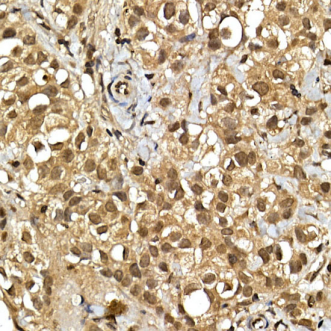

圖2 SQSTM1抗體免疫組化結(jié)果示意圖

(商品貨號:K005444P)